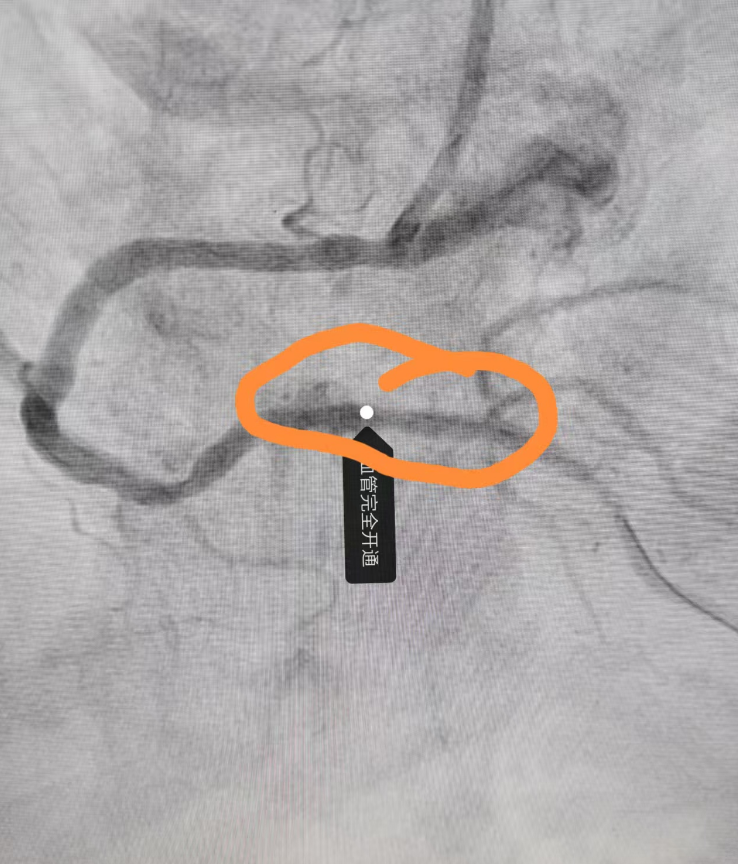

术中高效完成桡动脉穿刺,并即刻进行冠状动脉造影检查,影像学提示右冠状动脉远端完全闭塞。团队迅速评估病情,果断采用导丝技术成功通过闭塞病变段,随后使用预扩球囊对病变部位进行充分扩张,有效恢复血管管腔通畅性,在此基础上精准定位并成功植入支架一枚,实现右冠远端血运重建。术后造影显示血流恢复至TIMI 3级,手术顺利完成。

术后血管完全开通